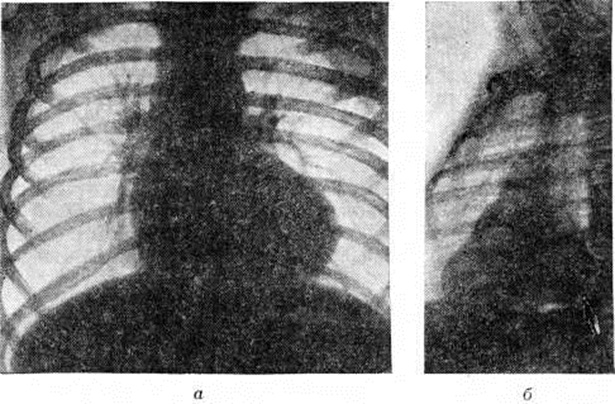

Относительно благоприятное состояние у большинства остальных больных может продолжаться несколько месяцев и обеспечивается существующей у новорожденных естественной полицитемией, наличием открытого артериального протока (смотри полный свод знаний) и относительно небольшим сопротивлением кровотоку, связанным со стенозом лёгочного ствола. Выраженные симптомы порока обычно развиваются в возрасте 4 — 6 месяцев У больных появляются отдышка (смотри полный свод знаний) и цианоз, усиливающиеся при физической нагрузке. Вследствие хронический гипоксемии развивается деформация концевых (дистальных фаланг пальцев в виде барабанных палочек (смотри полный свод знаний: Барабанные пальцы), ногти приобретают форму часовых стёкол. Увеличивается сеть венозных сосудов подкожной клетчатки. Выраженность этих признаков и полицитемия возрастают по мере увеличения объёма венозного сброса крови и степени цианоза. Дети начинают отставать в физическом развитии. Для отдыха занимают характерное положение на корточках. Наиболее грозными проявлениями порока являются приступы одышки, возникающие в результате внезапно развивающегося спазма артериального конуса правого желудочка. Во время приступа резко усиливаются одышка, цианоз, тахикардия (смотри полный свод знаний). Иногда приступ заканчивается развитием гипоксической комы (смотри полный свод знаний: Кома). При пальпации грудной клетки над областью сердца определяется грубое систолическое дрожание и усиленный верхушечный толчок. Границы сердца расширены умеренно. При аускультации тоны сердца громкие, первый тон на верхушке усилен. Наиболее характерным является ослабление второго тона над лёгочным стволом. При фонографическом исследовании второй тон над этой областью сердца расщеплен и его лёгочный компонент значительно снижен или отсутствует. Над сердцем выслушивается грубый систолический шум с максимальным звучанием в третьем-четвёртом межреберье слева от грудины. Шум проводится на сосуды шеи и на спину. На фонограмме зона шума имеет ромбовидную форму и занимает всю систолу (смотри полный свод знаний: Фонокардиография). В случаях, когда степень стеноза приближается к атрезии лёгочного ствола, интенсивность шума бывает минимальной или же он не выслушивается вообще. У больных с выраженным коллатеральным кровообращением над лёгкими прослушивается систолодиастолический шум в межлопаточном пространстве. На ЭКГ у всех больных отмечается отклонение электрической оси сердца вправо, а в грудных отведениях — признаки перегрузки правого желудочка и предсердия (смотри полный свод знаний: Электрокардиография). Рентгенологические исследование имеет важное значение для диагностики Фалло тетрада При этом лёгочные поля имеют обеднённый артериальный сосудистый рисунок, в прикорневой зоне нередко отмечаются хаотично расположенные тени коллатеральных сосудов. Тень сердца в переднезадней проекции у большинства больных увеличена незначительно, но имеет достаточно специфическую конфигурацию, напоминающую деревянный башмачок с закруглённой, приподнятой над диафрагмой верхушкой и западением в области лёгочного ствола (рисунок 1, а). В косых проекциях выявляются признаки увеличения правых и относительное уменьшение левых отделов сердца. Тень левого желудочка во второй косой проекции выглядит как небольшое выбухание с крутой кривизной (симптом шапочки) по задней поверхности сердечной тени (рисунок 1, б). Важное значение для окончательной диагностики Фалло тетрада, определения степени нарушения гемодинамики и уточнения анатомических изменений имеют дополнительные исследования — катетеризация полостей сердца (смотри полный свод знаний: Катетеризация сердца) и ангиокардиография (смотри полный свод знаний). Результаты этих исследований необходимы для решения двух важных практических вопросов — определения показаний к хирургическому лечению и выбор оптимального типа операции. Давление в лёгочном стволе при Фалло тетрада не превышает 10—20 миллиметров ртутного столба, а в правом желудочке оно равно давлению в левом желудочке или давлению в системной артерии. По изменению характера кривой в момент перехода кончика зонда из отдела с низким давлением в полость правого желудочка можно определить место расположения и степень выраженности стеноза. При клапанном стенозе регистрируется резкий перепад давления между лёгочным стволом и правым желудочком. Для инфундибулярного стеноза характерно сниженное давление на некотором протяжении кривой правожелудочкового давления. При комбинированном стенозе выявляется два уровня перепада давления. Определяя насыщение крови кислородом из проб, взятых в полостях сердца и системной артерии, устанавливают направление и величину внутрисердечного сброса, минутный объём правого и левого сердца. Ангиокардиографию необходимо выполнять в двух проекциях: переднезадней и боковой. Рентгеноконтрастное вещество вводят через катетер, расположенный в полости правого желудочка. На первых же кадрах ангиограммы выявляется основной признак порока — одновременное поступление рентгеноконтрастного вещества в лёгочный ствол и аорту (рисунок 2). Наряду с этим выявляется стеноз лёгочного ствола, который наиболее чётко может быть определён в боковой проекции. Когда при анализе ангиограмм, выполненных таким путём, возникают подозрения на существование дополнительных уровней стеноза на протяжении лёгочного ствола, необходимо проведение дополнительного исследования в аксиальной проекции. Лечение Фалло тетрада только хирургическое. Тауссиг (Н. В. Taussig) в 1944 год предложила для увеличения лёгочного кровотока и снижения гипоксемии накладывать анастомоз между ветвями аорты и лёгочного ствола. В 1944 год Блелок (A. Blalock) разработал и успешно выполнил в клинике операцию наложения анастомоза между левыми подключичной и лёгочной артериями. В последующем было предложено много вариантов операций. Наиболее эффективными оказались предложения Поттса (VV. J. Potts, 1946) — анастомоз бок в бок между нисходящей частью аорты и левой лёгочной артерией и Уотерстона (D. J. Waterston, 1962) — анастомоз между восходящей частью аорты и правой лёгочной артерией. Р. Брок (1948) предложил устранять стеноз лёгочного ствола специальным инструментом, вводимым в полость правого желудочка через прокол его передней стенки. Радикальную коррекцию порока, включая устранение стеноза и закрытие межжелудочкового дефекта, первым в условиях гипотермии (смотри полный свод знаний: Гипотермия искусственная) выполнил Скотт (Н. W. Scott) в 1954 год, а первый успешный результат получил Лиллихей (С. W. Lillehei, 1955), который для выполнения операции применил экстракорпоральное кровообращение. В том же году Кирклин (J. W. Kirklin) начал выполнять радикальные операции в условиях, когда и циркуляция и оксигенация крови осуществлялась с помощью аппарата искусственного кровообращения (смотри полный свод знаний: Искусственное кровообращение). Тем самым он завершил создание современной методики операции. Разработаны паллиативные и радикальные операции. Показания к ним определяются в зависимости от возраста и состояния больных. Радикальная операция считается методом выбора. Паллиативные операции, направленные на увеличение лёгочного кровотока и снижение гипоксемии, в настоящий, время выполняются у детей раннего возраста и больных, находящихся в очень тяжёлом состоянии. Но и в этих случаях они являются лишь первым этапом лечения Фалло тетрада В последующем при улучшении общего состояния производят радикальную коррекцию. Среди многих типов паллиативных операций практическое значение сохраняют две. 1. Операция Блелока — Тауссиг, которая обязательно выполняется на стороне, противоположной расположению дуги аорты. Грудную клетку вскрывают боковым доступом в четвёртом межреберье. После выделения левой подключичной артерии и левой лёгочной артерии в корне лёгкого между ними накладывают анастомоз по типу конец в бок (рисунок 3). 2. Операцию Уотерстона в модификации Кули (D. A. Cooly) осуществляют правосторонним переднебоковым доступом в четвёртом межреберье. Внутриперикардиально выделяют правую лёгочную артерию и восходящую часть аорты. Участок задней поверхности аорты пристеночно отжимают зажимом, которым одновременно пережимают и проксимальный конец правой лёгочной артерии (рисунок 4). Дистальный конец артерии перекрывают турникетом под верхней полой веной. В прилегающих отделах сосудов делают разрез и накладывают анастомоз бок в бок диаметром 4—5 миллиметров. Преимущество этих операций по сравнению с другими видами паллиативных вмешательств состоит в их высокой (на протяжении 3—5 лет) эффективности. Кроме того, они меньше, чем другие, затрудняют выполнение в последующем радикальной операции. Послеоперационная летальность составляет 2—5%. Радикальную операцию выполняют на открытом сердце в условиях искусственного кровообращения (смотри полный свод знаний) и кардиоплегии (смотри полный свод знаний). Устраняют клапанный стеноз, тщательно иссекают все мышечно-фиброзные структуры, образующие препятствия на пути поступления крови из правого желудочка в малый круг кровообращения. Гипоплазированные участки правого желудочка, фиброзного кольца, лёгочного ствола и его ветвей расширяют до должных размеров путём вшивания заплат из аутоперикарда или синтетической ткани. Дефект межжелудочковой перегородки закрывают заплатой, подшиваемой к его краям непрерывным или П-образными швами. Послеоперационная летальность колеблется от 8 до 15% в зависимости от тяжести исходного состояния больного и объёма произведённой реконструкции, Правильно выполненная операция обеспечивает нормализацию гемодинамики и хорошие отдалённые результаты. Смотри полный свод знаний: Лёгочный ствол, Пороки сердца врождённые, Сердце.